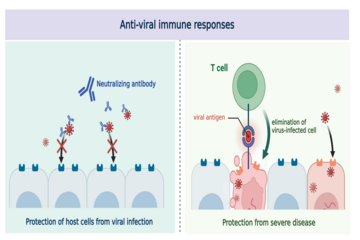

2024-01-12Evolution of the human immune system in the post-Omicron era

2024-01-12Evolution of the human immune system in the post-Omicron era